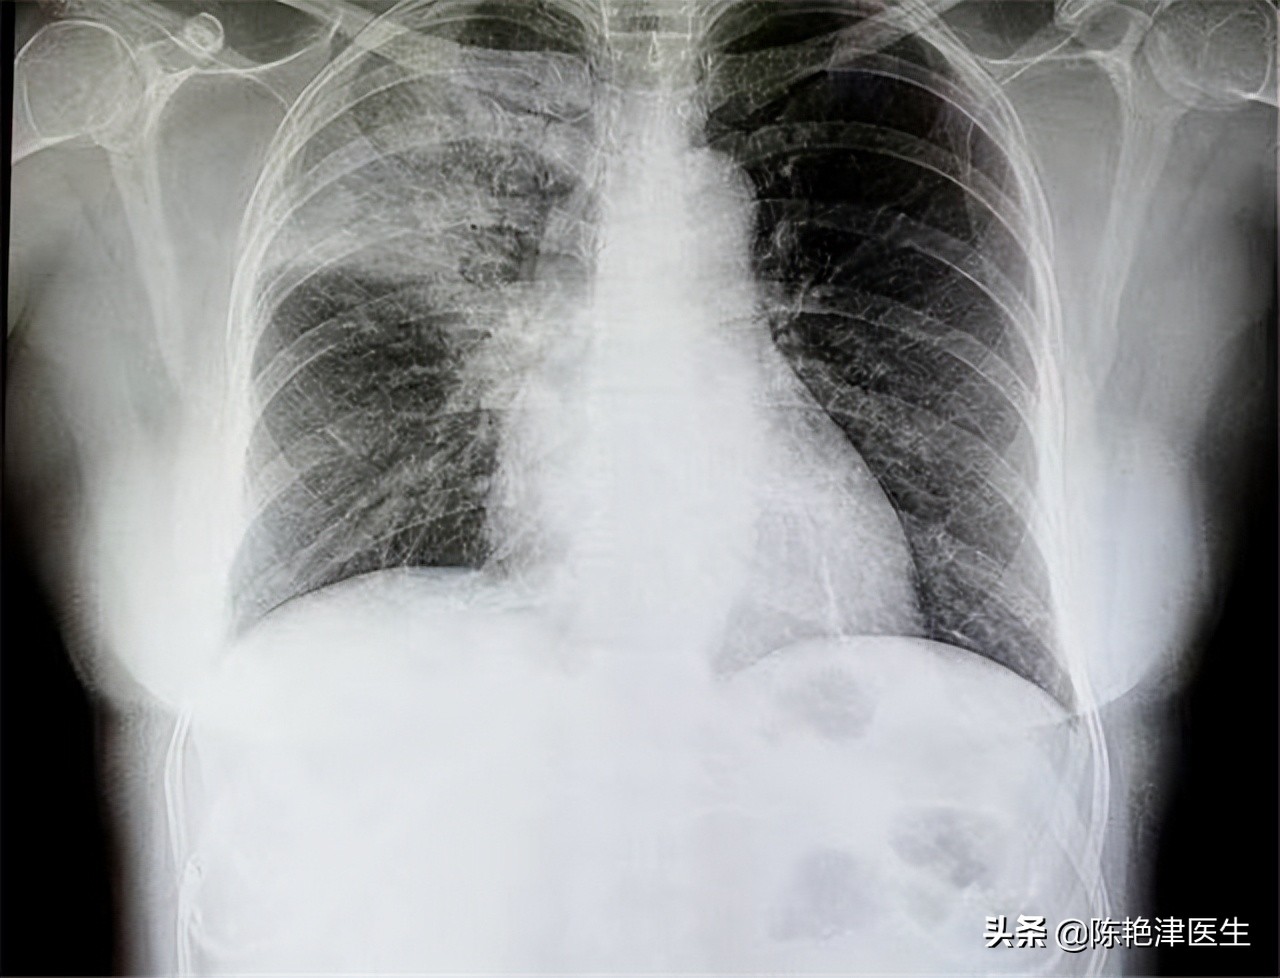

第②个:X光片筛查肺癌

X光片是指利用X射线穿透胸部成像的影像诊断技术,主要用于胸廓,纵膈,肺部,心脏等组织结构的观察, X光片只能观察骨骼和组织的结构,无法准确观察组织器官或骨骼内部否发生癌变,如果细胞侵犯肺外部组织,并且在肺外部形成巨大的肿瘤,那么X光片可以筛查出来。

但是当肺癌已经影响整个肺部形态时,说明肺癌已达到晚期,肺癌早期基本发生在肺部内,几乎不会影响外部肺形态。 因此X光片筛查早期肺癌几乎没有任何作用,有筛查肺癌需求的人群可以通过胸部CT。